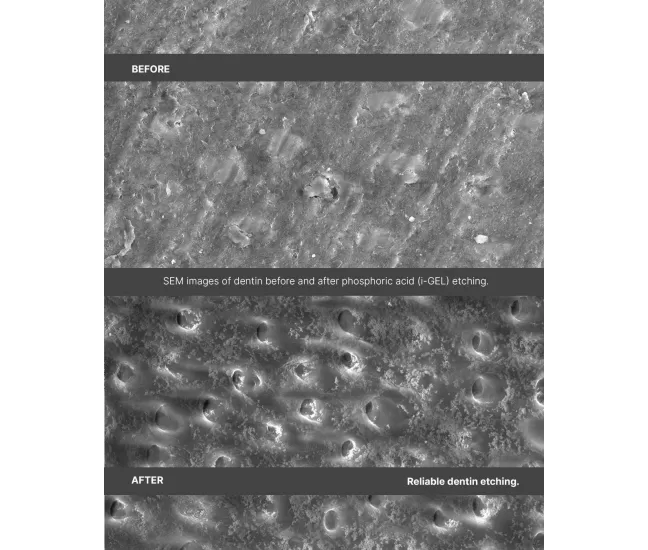

37% phosphoric acid effectively removes the smear layer and opens dentinal tubules for optimal bonding;